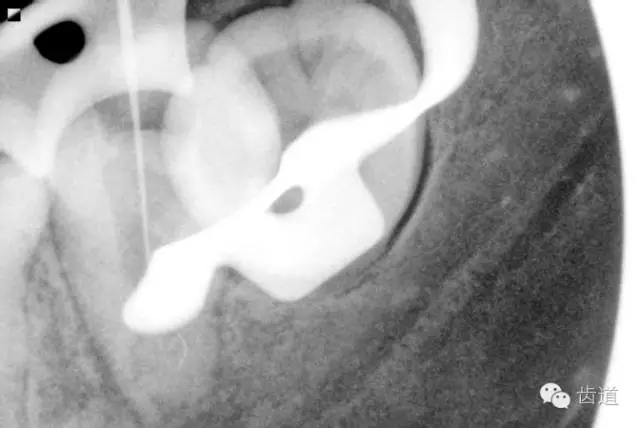

3. 術(shù)前CBCT片:

在水平斷層上,可見37根管在根尖三分之一為彎曲偏向頰側(cè)的C型,存在近遠(yuǎn)中兩個(gè)主根管,中間峽部相連;在矢狀斷層上,可見37根管遠(yuǎn)中根尖孔擴(kuò)大,遠(yuǎn)中根尖狹窄處位于離解剖根尖約1mm處